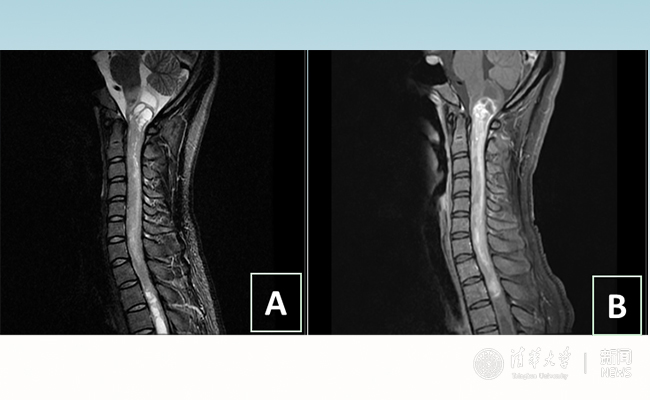

2018.01拯救“90后”女孩 清华长庚神经外科切除20多公分髓内肿瘤

“愿得韶华刹那,开得满树芳华。”27岁的患者小甜(化名)在beat365官方唯一入口附属北京清华长庚医院成功进行了手术,神经外科主任王贵怀为其切除了自延髓至胸髓的长达20余公分的脊髓内肿瘤。1月9日,小甜顺利出院,再续芳华!